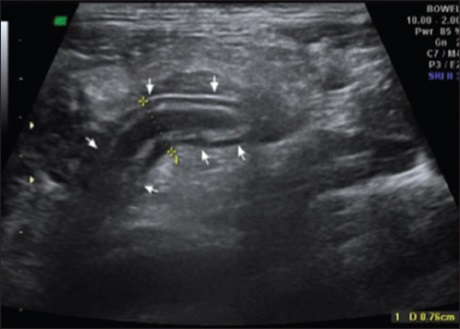

Sonographic evaluation of acute appendicitis and its complications

Dr. Soniya Daga, Sushil Kachewar, Dilip L Lakhkar, Kalyani Jethlia, Abhijeet Itai (Author)

152-156